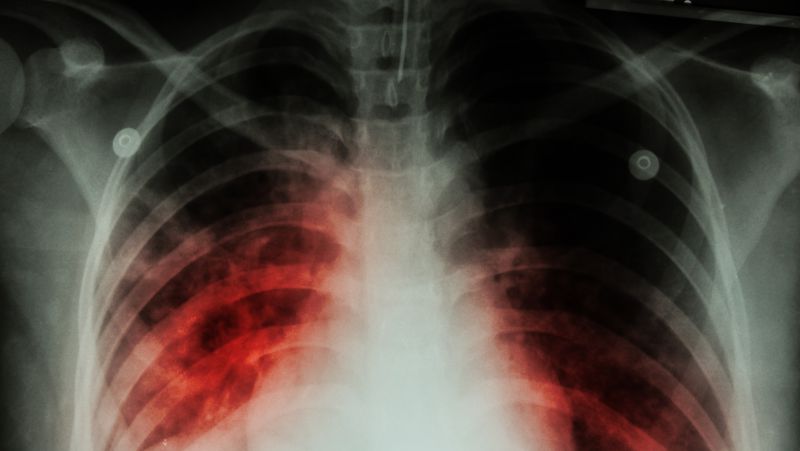

影像学的诊断主要是通过胸部CT,通过各种影像的手段确认肺部是否存在占位或者肿块、结节。

目前,筛查肺癌最常用、最标准的手段还是胸部CT检查。因为胸部CT检查肺癌的敏感度非常高,哪怕只有两三毫米的肺部小结节, 就都能非常敏锐的发现。

所以如果进行胸部CT检查,发现肺部有肿块,有结节,有微小结节这些情况存在的时候,一定要高度重视。要确认是不是肺癌,首 先要找专科的医生进行判断,并根据医嘱进行随访观察或者进行活检、穿刺、手术等等,来确认肺部的结节是不是肺癌。